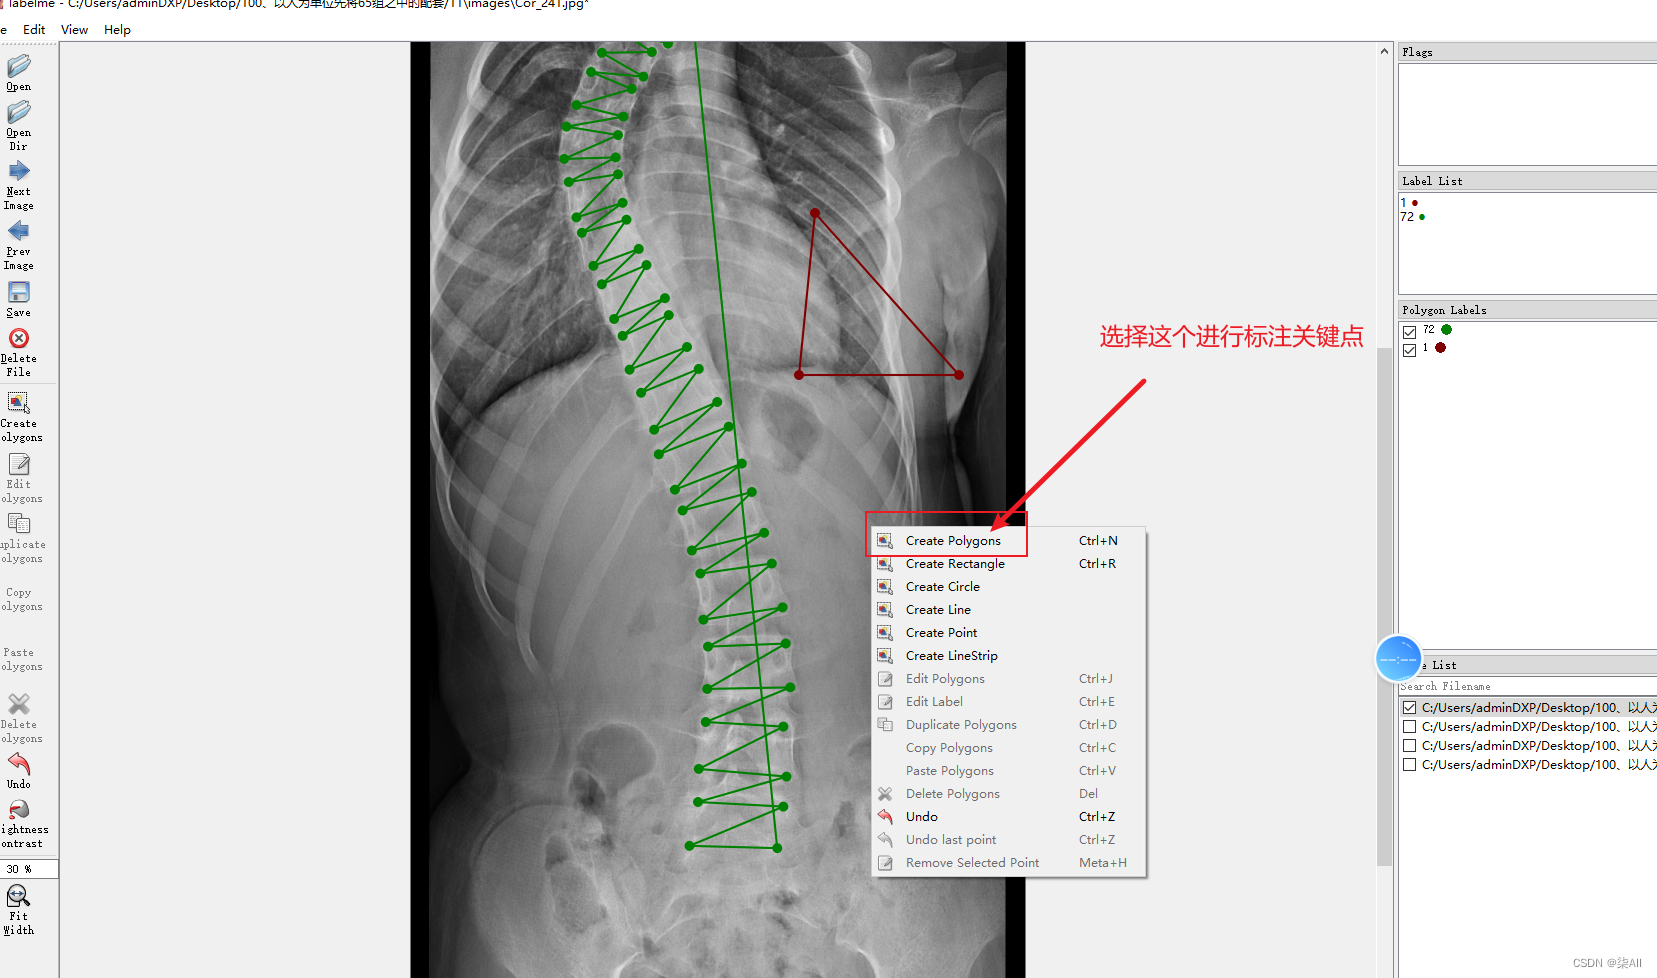

- 2、开始标注(以冠状位为例,其他方位是一样的操作,视频教程)

- 3、冠状位标注结果

2、开始标注(以冠状位为例,其他方位是一样的操作,视频教程)

冠状位关键点标注教程

3、冠状位标注结果